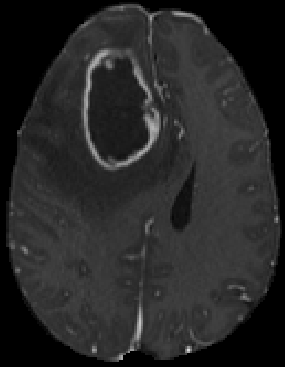

Figure 8 presents the predicted segmentations of cases 01774-000, 00521-001 and 00190-000. In the first two cases our models performed poorly (Figure 8 first and second rows). The ET is not detected by our solutions, which leads to a value 0 for this label. This could be due to the quality of the acquired scans, as this strongly influences the performance of deep learning models. For future improvements, more synthetic data can be generated with the specific cases of poorer scans. The last row of Figure 8 shows a case with an almost perfect segmentation. Our solution archived DSC above 0.9 for most of the validation cases.

Refer to caption

(a) T1CE

(b) FLAIR

(c) Prediction

(d) T1CE

(e) FLAIR

(f) Prediction

(g) T1CE

(h) FLAIR

(i) Prediction

Figure 8: Samples of the validation set segmented by our best ensemble model. Columns display the T1CE, T2-FLAIR, and the overlay of our predicted segmentation on the T1CE scan. Red corresponds to NCR, green ED, and blue ET. The first row presents the case with ID 01774-001, the second row the worse prediction (ID 00521-001), and the third row the best prediction (ID 00190-00).